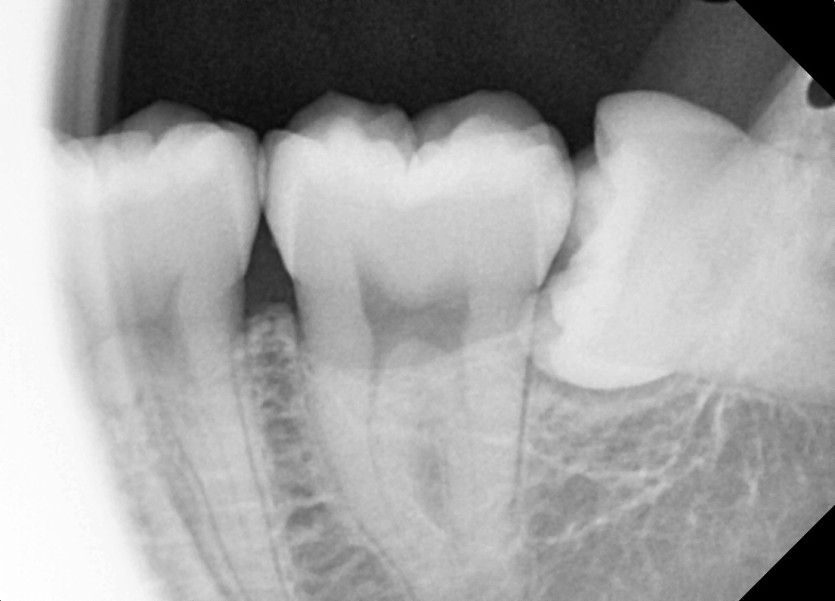

#18,28,38,48 사랑니 발치 (#19과잉치 포함)

구강 외과 전문의가 당일 발치했습니다.